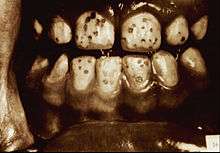

It appears as a range of visual changes in enamel[4] causing degrees of intrinsic tooth discoloration, and, in some cases, physical damage to the teeth. The severity of the condition is dependent on the dose, duration and age of the individual during the exposure.[1] The "very mild" (and most common) form of fluorosis, is characterized by small, opaque, "paper" white areas scattered irregularly over the tooth, covering less than 25% of the tooth surface. In the "mild" form of the disease, these mottled patches can involve up to half of the surface area of the teeth. When fluorosis is moderate, all of the surfaces of the teeth are mottled and teeth may be ground down and brown stains frequently "disfigure" the teeth. Severe fluorosis is characterized by brown discoloration and discrete or confluent pitting; brown stains are widespread and teeth often present a corroded-looking appearance.[1]

| Severe | 5 | All enamel surfaces are affected and hypoplasia is so marked that the general form of the tooth may be affected. The major diagnostic sign of this classification is discrete or confluent pitting. Brown stains are widespread and teeth often present a corroded-like appearance. |